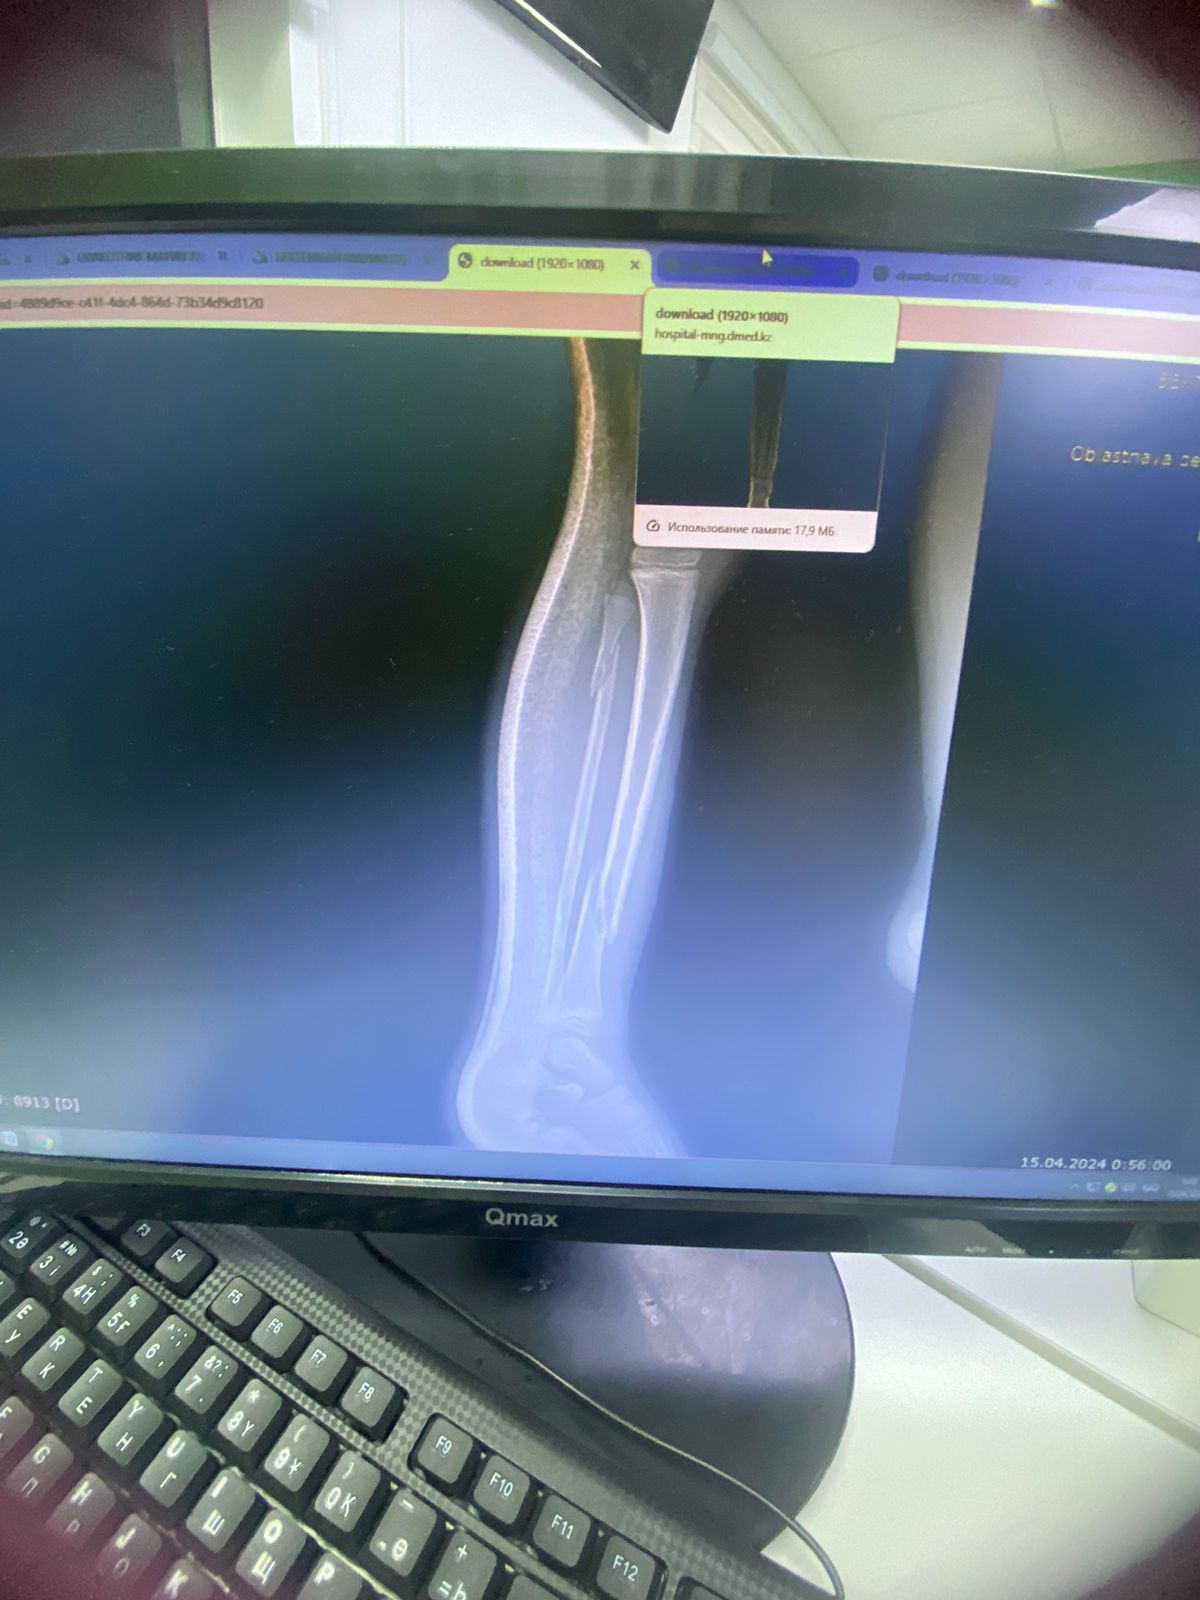

Фото предоставлено Жаксыгуль Исатаевой

Пострадавший в результате происшествия получил ушибы, ссадины, травму головы, гематомы. Самым серьезным увечьем стал перелом голени в двух местах.

- В больнице в месте перелома сделали операцию, которая длилась четыре часа. Я не хотела, чтобы ему делали ее, но врачи сказали, что кости нужно собрать, - добавила Жаксыгуль Исатаева.

По словам Жаксыгуль Исатаевой, впереди у сына вторая операция на ногу.